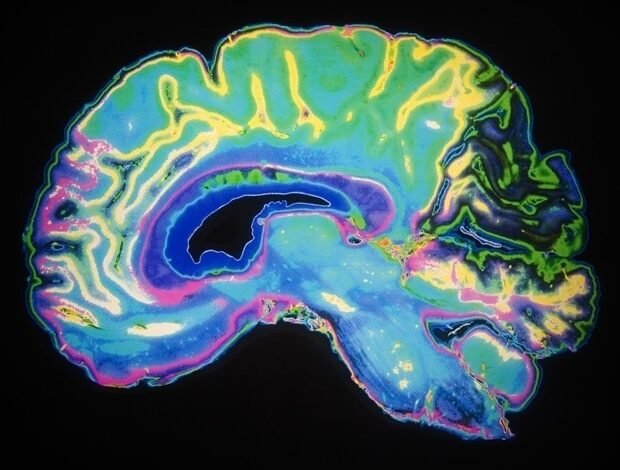

A origem de algumas doenças neurológicas e psicológicas, como autismo, transtorno bipolar, depressão e algumas doenças degenerativas neurológicas, a paralisia de Alzheimer e Parkinson, pode ser encontrada em estágios muito precoces da formação cerebral no feto. Ou seja, antes do reconhecimento anterior, de acordo com um estudo realizado pelo Hospital Del Mar para Pesquisa e Universidade de Yale, publicado em Comunicações da natureza.

Para fazer isso, eles usaram uma lista de aproximadamente 3000 genes associados a doenças neurológicas mentais, doenças degenerativas neurológicas, deformidades corticais e simulação do efeito de alterá -las nas células envolvidas no desenvolvimento do cérebro. Os resultados indicam que muitos desses genes Já está funcional durante os estágios iniciais do feto Desenvolvimento em células -tronco, cepas que constroem o cérebro, criam neurônios e suas estruturas de apoio.

Durante o estudo, redes regulatórias específicas foram simuladas para cada tipo de célula participando do crescimento do cérebro Para descobrir como estimular ou cancelar a ativação de genes que foram analisados associados a várias doenças cerebrais nas células do antecessor em seus vários estágios. Isso lhes permitiu monitorar a importância de cada gene no surgimento de ajustes que causam várias doenças. O cardápio varia de microcefalia e hidrocefalia a autismo, depressão, transtorno bipolar, perda de apetite ou esquizofrenia e também inclui Alzheimer e Parkinson.

Em todas essas doenças, os genes que participam dos estágios iniciais do desenvolvimento do cérebro são encontrados quando os neurônios são encontrados. “Estamos cobrindo uma ampla gama de doenças das quais o cérebro pode sofrer e analisamos como os genes que participam dessas condições se comportam nos neurônios”, acrescenta Xoel Mato-Blanco, pesquisador do Instituto de Pesquisa do Hospital Del Mar. Ao mesmo tempo, indica que o trabalho “determina as janelas de tempo e os tipos de células onde o trabalho desses genes é mais relevante e indica quanto tempo e onde a função desses genes deve ser direcionada”.

O Dr. Sanbiri diz que a presença dessas informações é “benéfica para entender a origem das doenças que afetam o córtex cerebral, ou seja, como as mudanças genéticas são traduzidas para essas doenças”. Compreender esses mecanismos e o papel de cada gene em cada doença pode ajudar a desenvolver tratamentos direcionados que funcionam neles e abrir as chances de genes Tratamento e tratamentos pessoais.